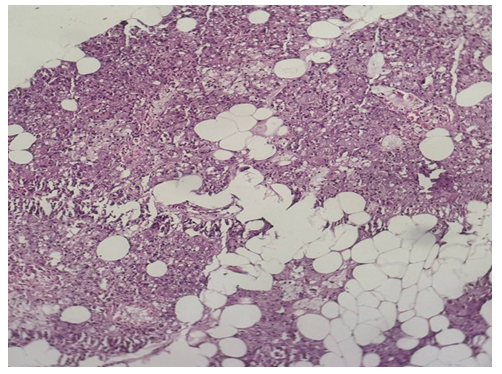

| Picture 2. Surgically resected specimen of salivary gland tumor. Histological appearance of pleomorphic adenoma (mixed tumor), localized in the left parotid gland (1 case; No. 2755). The tumor demonstrates biphasic morphology with epithelial and myoepithelial components embedded in a heterogeneous myxoid–chondroid stroma (H&E stain) |

Morphological description: The section reveals a well-circumscribed salivary gland neoplasm composed of uniform epithelial cells with round to oval nuclei and scant cytoplasm. The tumor grows in a solid and trabecular pattern with minimal cellular pleomorphism. Adipose tissue infiltration is seen at the periphery, but the neoplasm maintains a distinct border from surrounding structures. No chondromyxoid stroma or mixed tissue elements are identified, which distinguishes this tumor from pleomorphic adenoma. Figure 3. Histological section of monomorphic adenoma of the submandibular gland showing uniform epithelial cells arranged in solid and trabecular patterns with sharp demarcation from adjacent adipose tissue. No stromal heterogeneity is observed (H&E stain, ×20). | Figure 4a. Pleomorphic adenoma |

Morphological description: Histological examination reveals a well-circumscribed tumor with a characteristic mixed architecture. Epithelial and myoepithelial cells form irregular duct-like and trabecular structures. The stroma is markedly heterogeneous, demonstrating areas of myxoid, chondroid, and fibrous components. This biphasic pattern with variable stromal composition is a hallmark of pleomorphic adenoma. No signs of malignant transformation are seen in the examined section. Figure 4a. Pleomorphic adenoma of the parotid gland showing mixed epithelial and myoepithelial cell proliferation with heterogeneous stromal components, including myxoid and chondroid areas (H&E stain, х10).  | Figure 4b. Pleomorphic adenoma |

Morphological description: Microscopic examination demonstrates epithelial and myoepithelial cell proliferation forming duct-like and solid structures embedded within a myxochondroid stroma. The stroma exhibits cartilaginous differentiation with lacunae containing chondrocyte-like cells, a typical feature of pleomorphic adenoma. Foci of hemorrhage and vascular congestion are also observed. The biphasic pattern of epithelial and stromal elements further supports the diagnosis of pleomorphic adenoma. Figure 4b. Pleomorphic adenoma of the parotid gland showing epithelial and myoepithelial proliferation embedded in myxochondroid stroma with chondrocyte-like cells. Biphasic morphology is characteristic of pleomorphic adenoma (H&E stain, х20). | Figure 4c. Pleomorphic adenoma |